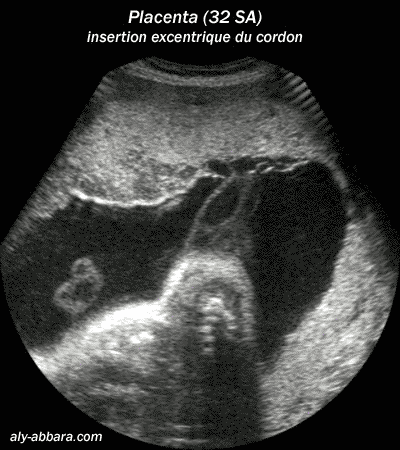

Placenta d'une grossesse à 32 semaines d'aménorrhée avec insertion excentrique (ou paramétriquement)

du cordon ombilical sur la face placentaire ftale